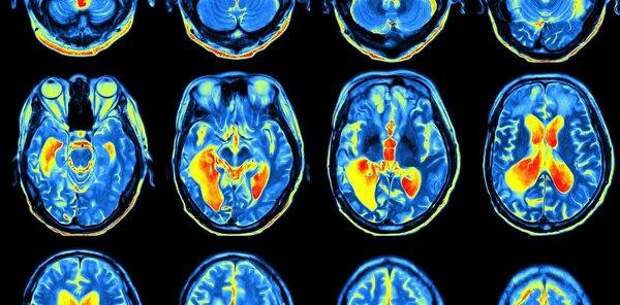

Сегодня ученые достигли значительного прогресса в понимании мозговой деятельности и того, как она влияет на поведение человека. Но никто до сих пор не смог объяснить, как все это приводит к чувствам, эмоциям и переживаниям. Как передача электрических и химических сигналов между нейронами заставляет формироваться ощущение боли или воспринимать красный цвет. Исследователи все больше склоняются к тому, что традиционные научные методы никогда не смогут ответить на эти вопросы. К счастью, существует альтернативный подход, который в конечном итоге может раскрыть тайну. Многие ученые недооценивают глубину проблемы, полагая, что просто нужно продолжить изучение физических структур мозга, чтобы понять, каким образом они производят сознание. Однако проблема определения природы этого физического явления радикально отличается от любой другой научной проблемы. Одна из причин состоит в том, что сознание ненаблюдаемо. Нельзя заглянуть в чью-то голову и увидеть чувства и переживания. Если бы мы просто отклонялись от того, что мы можем наблюдать с точки зрения третьего лица, у нас не было бы никаких оснований для постулирования сознания вообще, поясняют ученые. Лучшее, что могут сделать исследователи в этом случае, - это соотнести ненаблюдаемый опыт с наблюдаемыми процессами, сканируя мозг людей и полагаясь на их отчеты, касающиеся их личного сознательного опыта. С помощью этого метода можно установить, например, что невидимое чувство голода коррелирует с видимой активностью в гипоталамусе мозга. Но накопление таких корреляций не составляет теории сознания. В конечном итоге специалисты хотят объяснить, почему сознательный опыт связан с деятельностью мозга. Сегодня некоторые ученые склоняются к теории «панпсихизма» - древнее представление о том, что сознание является фундаментальной и вездесущей особенностью физического мира. Но в «новой волне» панпсихизма отсутствуют мистические коннотации, свойственные прошлым представлениям. Существует только материя - ничего духовного или сверхъестественного - но материю можно описать с двух позиций. Физическая наука описывает материю «извне» с точки зрения ее поведения, но материя «изнутри» состоит из форм сознания. Это означает, что разум — это материя, и даже элементарные частицы проявляют основные формы сознания, считает философ Дэвид Чалмерс. По его словам, сознание может варьироваться по сложности. «У нас есть веские основания полагать, что сознательный опыт лошади гораздо менее сложен, чем у человека, и что сознательный опыт кролика менее сложен, чем у лошади», - отметил он. «По мере того, как организмы становятся проще, может существовать момент, когда сознание внезапно отключается, но также возможно, что оно просто исчезает», - добавил он. Таким образом, панпсихизм предлагает нам простой способ интеграции сознания в наше научное мировоззрение, уверен философ. В то время как нынешний научный подход вообще не предлагает никакой теории - только корреляции - традиционная альтернатива, утверждающая, что сознание находится в душе, приводит к гипотезе, согласно которой разум и тело различны. «Панпсихизм избегает обеих этих крайностей, и именно поэтому некоторые из наших ведущих нейробиологов теперь воспринимают его как лучшую основу для построения науки о сознании», - заключил он. Материал подготовила Татьяна Артюхова